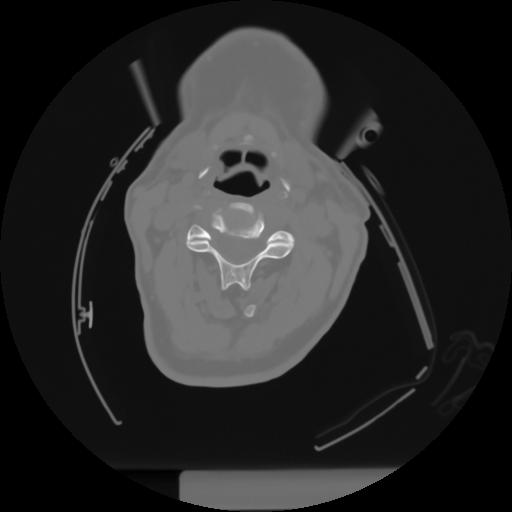

10 P.BLANDAS,,Axial,2.0,P.BLANDAS,,